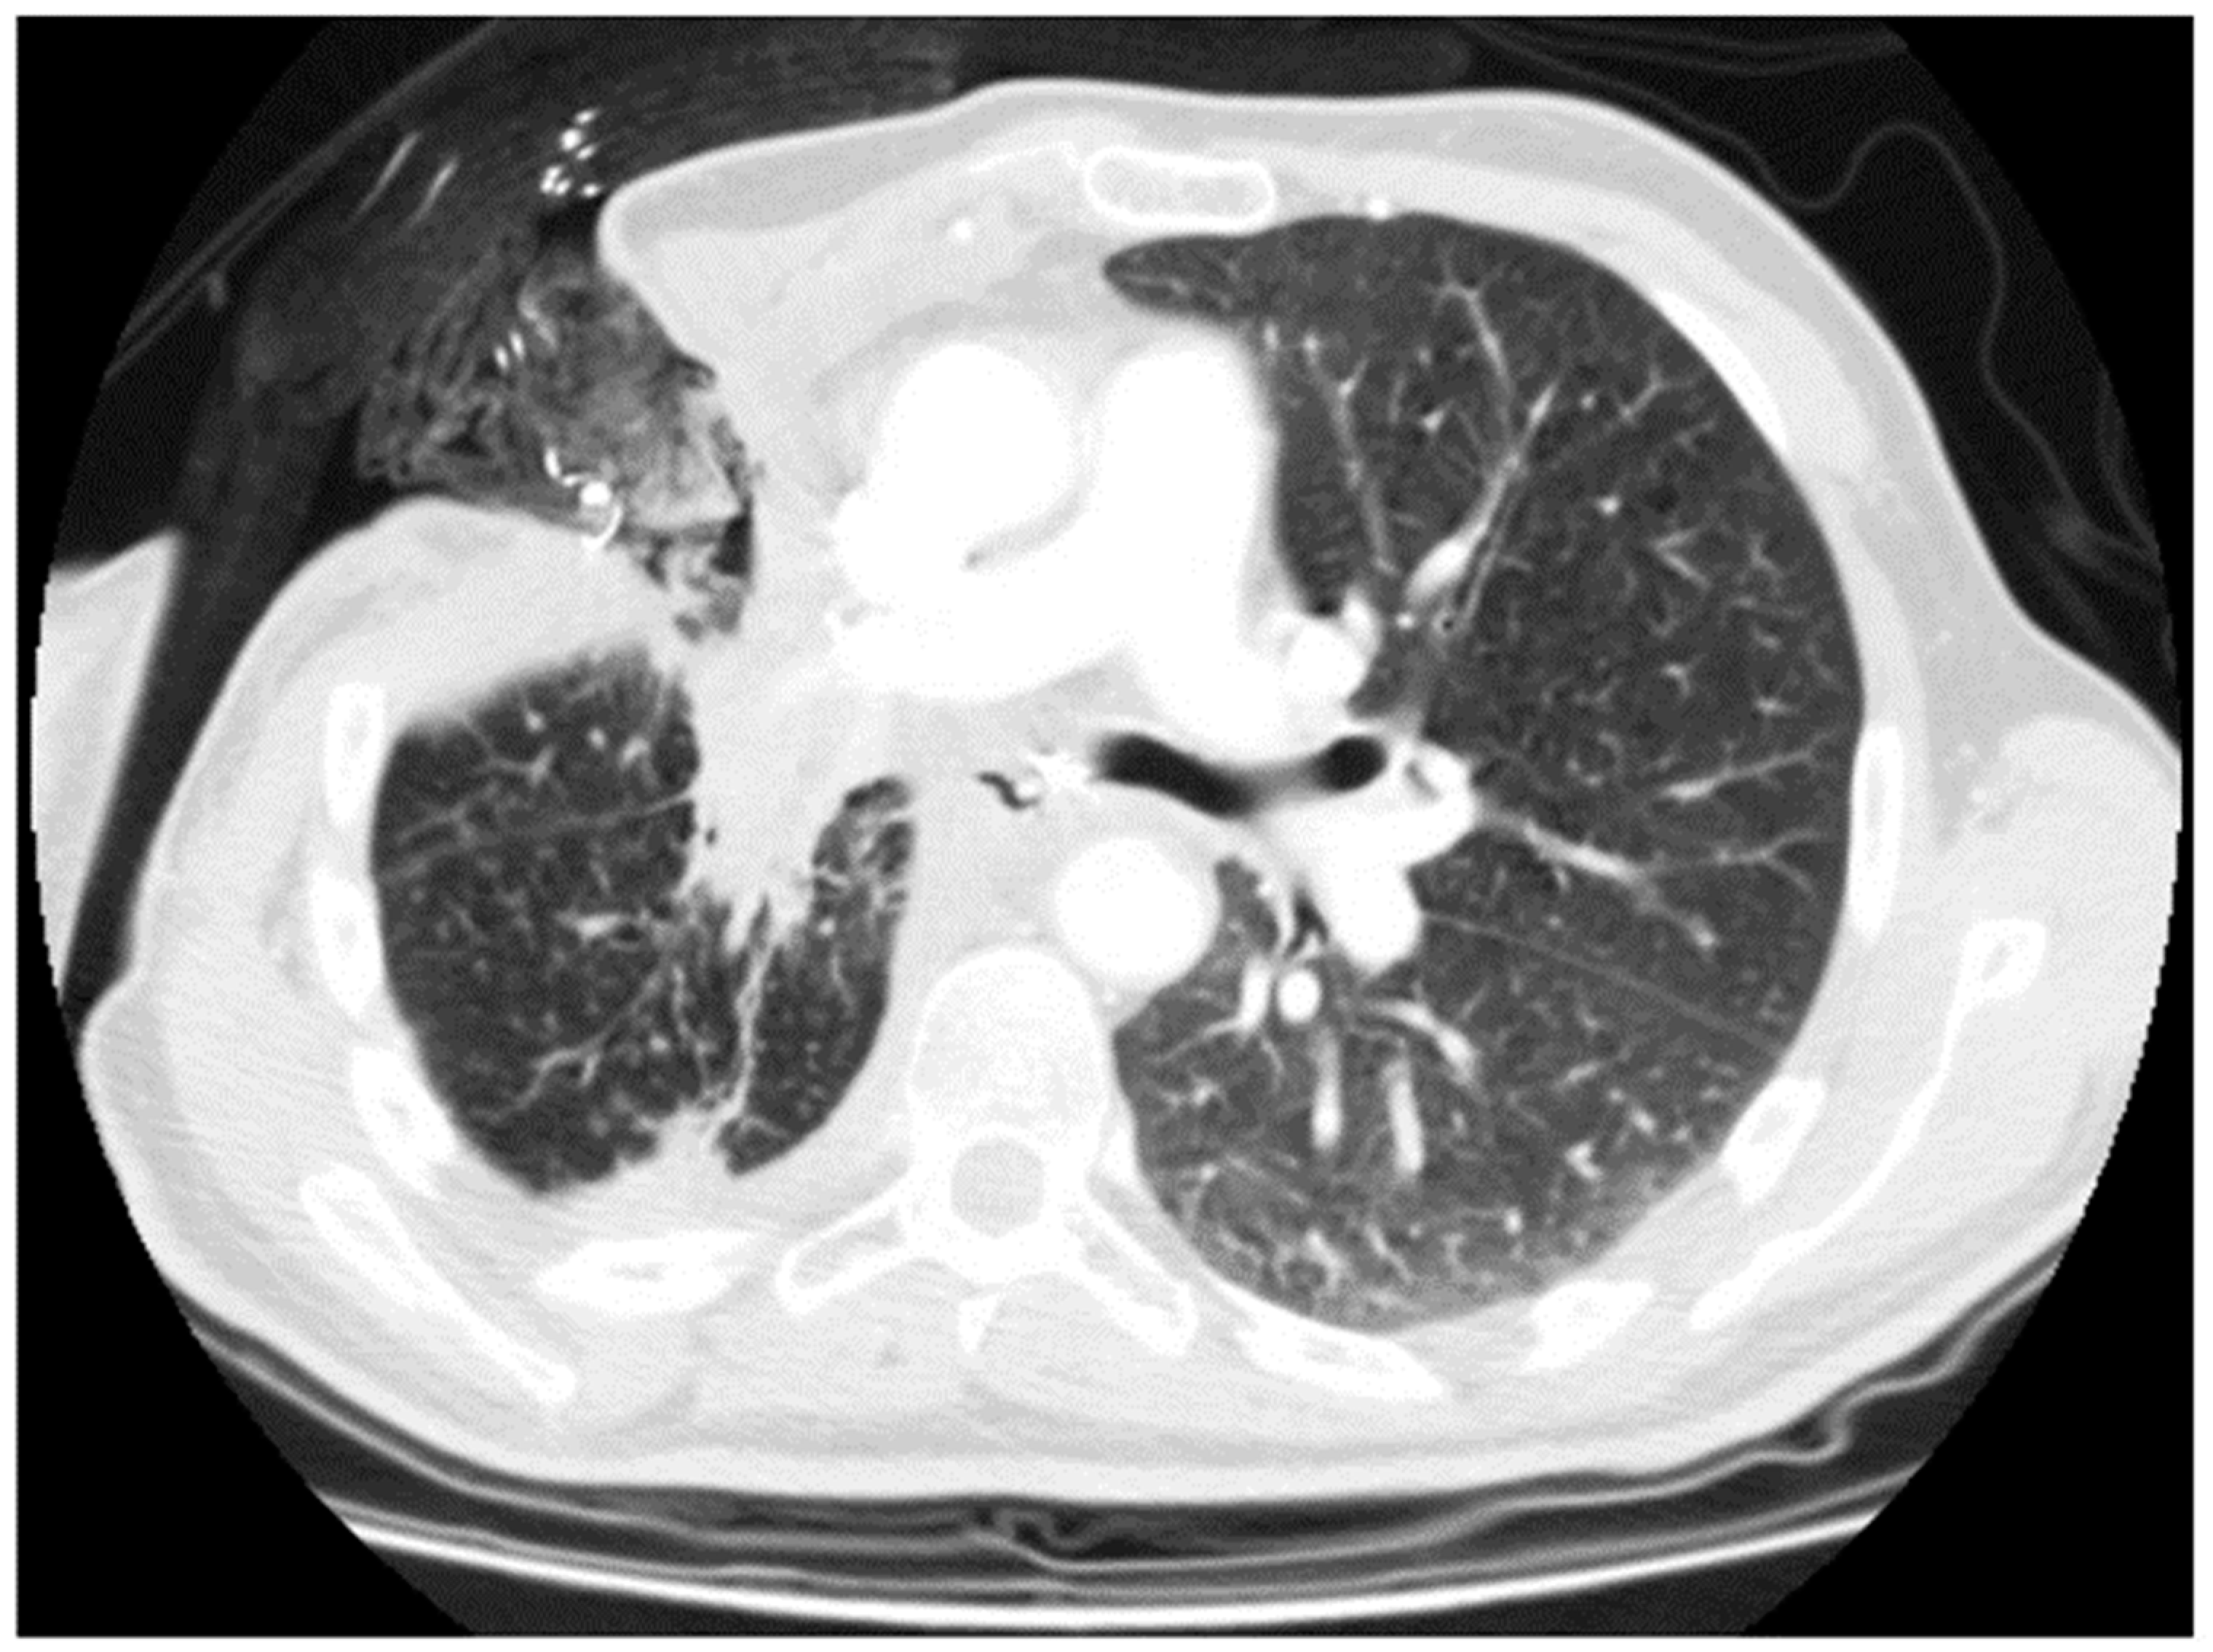

2.3. New Therapeutic Horizons: Percutaneous Treatment of Small and Late BPF